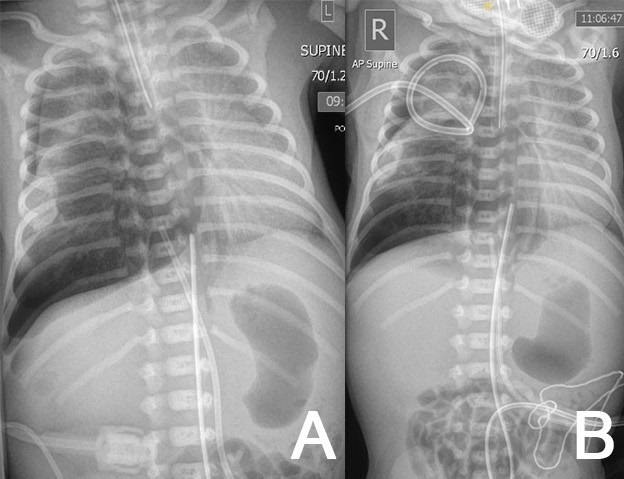

A baby boy (twin) was born at 28+3 weeks of gestation, to a 33-year-old mother. Due to cord prolapse, an emergency lower segment cesarean section was undertaken. APGAR scores were 2, 6, and 8 at 1, 5, and 10 minutes, respectively. Spontaneous respiration was attained after 4 minutes of the bag and mask inflation breaths. Due to apneic episodes on CPAP, he was intubated using a size 3 ETT with conventional ventilation at a peak pressure of 24 cmH2O and positive end-expiratory pressure (PEEP) of 5 cmH2O. Surfactant was administered. Chest radiography (CXR) showed increased left lung opacity and low-lying ETT tip. This was withdrawn for effective ventilation.

At 3 hours of age, due to sudden loss of chest movements and volumes on ventilation, the neonate was re-intubated. There was ongoing respiratory distress and CXR confirmed a right-sided tension pneumothorax (Fig. 1A). Needle aspiration followed by tube thoracocentesis (TT) with the underwater seal was undertaken (Fig. 1B) . The drain was placed on low-flow suction. One hour later, further desaturation and transillumination indicated a large residual pneumothorax, necessitating a second chest drain, also placed on low-flow suction. Ventilation improved and he remained on 25% FiO2.

An iatrogenic tracheobronchial injury was suspected. On day 2, he developed a greater oxygen requirement; transillumination and radiography confirmed persistent pneumothorax, this time with pneumomediastinum and pneumoperitoneum, requiring a third chest drain. He was then transferred to the regional pediatric center. After a fourth TT (Fig. 2B) due to a massive ongoing air leak (Fig. 2A), high-frequency oscillatory flow ventilation (HFOV) was tried.

On day 5, CXR showed improvement. 2 non-bubbling drains were clamped and later removed. However, due to clinical deterioration and re-accumulation on days 5, 6, and 7, three other TTs were required, with subsequent improvement. A repeat echocardiogram demonstrated signs of pulmonary hypertension. Nitric oxide, dobutamine, and adrenaline were adjusted to allow pulmonary vascular circulation dilatation and reduce systemic vasoconstriction and echocardiogram findings improved.

Extracorporeal membrane oxygenation was not deemed suitable and conservative management continued. The 5 chest drains remained in situ with varying effectiveness. On day 10, dobutamine was stopped, nitric oxide was weaned off and HFOV was de-escalated to conventional ventilation at a peak pressure of 26 cmH2O and PEEP of 7 cmH2O. Only one drain bubbled continuously and then was removed on day 13.

Chest and abdominal radiographs showing right-sided pneumothorax (first diagnosis) – before (A) and after (B) drain 1.

Figure 2

Chest and abdominal radiographs showing right-sided pneumothorax, pneumomediastinum, and pneumoperitoneum (massive air leak)– before (A) and after (B) drain 4.